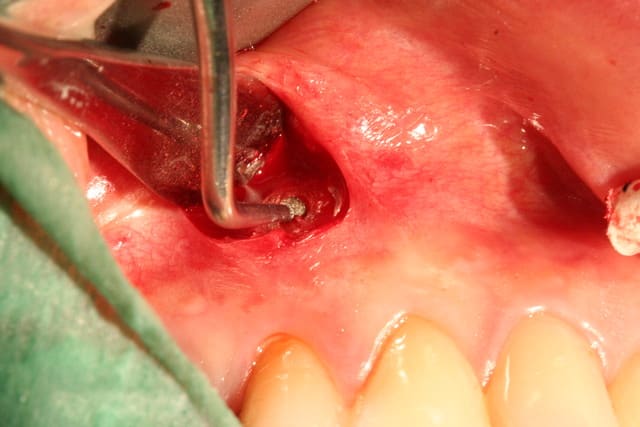

Je viens de faire l'extraction ce matin.

Je rage de ne pas l'avoir fait encore plus tôt car c'est bien ce que je craignais, toute la table externe a été bouffée par l'infection...

J'ai cureté très soigneusement et irrigué puis mis matériaux de comblement pour limiter l'effondrement en vestibulaire.

Je corrige; curetage le plus soigneux possible, curettes, fraise boule...

Si j'avais eu plus de temps, j'aurai fais un lambeau et tout et tout avec membrane .

1/2 Heure seulement de libre ce matin. Mea Culpa mon amibe.

Le Bio matériau est du RTR de chez Septodont sous forme de cône pour être inséré dans les alvéoles toutes fraîches.